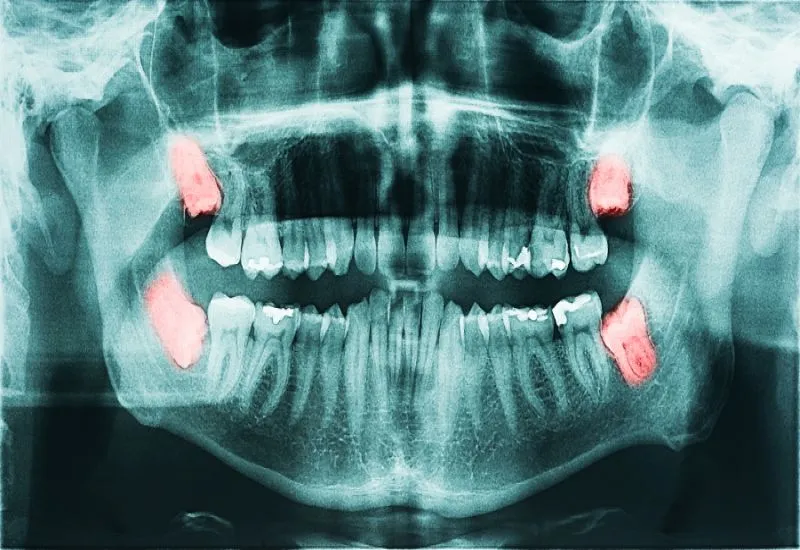

Zęby mądrości, znane również jako ósemki, to trzecie zęby trzonowe, które wyrzynają się jako ostatnie w jamie ustnej. Ich pojawienie się często budzi wiele obaw, i nie bez powodu. Główną przyczyną problemów z ósemkami jest brak wystarczającej ilości miejsca w łuku zębowym. Współczesny człowiek ma często mniejsze szczęki niż nasi przodkowie, a ósemki po prostu nie mieszczą się w jamie ustnej. Może to prowadzić do ich zatrzymania (pozostania w kości), nieprawidłowego wzrostu (np. pod kątem), a w konsekwencji do silnego bólu, stanów zapalnych dziąseł, uszkodzenia sąsiednich zębów, a nawet powstawania torbieli. Nierzadko konieczna jest ich ekstrakcja.

Zęby mądrości zazwyczaj zaczynają wyrzynać się między 17. a 25. rokiem życia, choć zdarza się, że pojawiają się później lub wcale. To właśnie dlatego nazywamy je "zębami mądrości" wyrastają w wieku, gdy człowiek jest już uznawany za dorosłego. Warto wiedzieć, że proces ten nie zawsze musi być bolesny. U niektórych osób ósemki wyrzynają się bez żadnych dolegliwości, podczas gdy u innych towarzyszy im znaczny dyskomfort, obrzęk, ból, a nawet gorączka. Jeśli odczuwasz silny ból lub inne niepokojące objawy, zawsze warto skonsultować się ze stomatologiem.

Hipodoncja i agenezja: co robić, gdy brakuje zawiązków zębów stałych?

Na drugim biegunie anomalii zębowych znajduje się hipodoncja, zwana również agenezją zębów. Jest to wrodzony brak zawiązków jednego lub więcej zębów, co oznacza, że dany ząb nigdy się nie wykształci. Najczęściej dotyczy to zębów stałych, zwłaszcza siekaczy bocznych, drugich przedtrzonowców czy właśnie zębów mądrości. Jeśli zauważymy, że dziecko w wieku 13-14 lat nie ma pełnego uzębienia stałego, może to być sygnał do podejrzenia hipodoncji. W takich przypadkach niezbędna jest konsultacja z ortodontą i wykonanie diagnostyki radiologicznej, aby zaplanować odpowiednie leczenie, które często obejmuje leczenie ortodontyczne lub protetyczne w celu uzupełnienia braków i zapewnienia prawidłowej funkcji zgryzu.